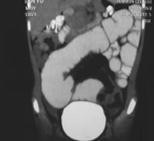

【体格检查】 腹部体查未发现明显阳性指征。上消化道造影发现钡剂走行至约第4组小肠位置时肠管明显扩张,最宽直径达5 cm左右,见频繁逆蠕动,造影剂通过受阻,似可见一类圆形充盈缺损,提示不全肠梗阻。 【辅助检查】 腹部彩超提示右侧腹部局部小肠扩张,肠壁增厚,局部肠壁似见连续不完整,与之紧密相连可见一个混合回声团块;腹部增强CT提示空回肠交界及部分回肠明显扩张于膀胱上方,通过受阻,肠壁明显不规则增厚,伴显著异常强化,周围可疑异常强化病灶。

【诊断】 腹腔占位,且与小肠关系密切。 【治疗】 结合病史、体征、相应实验室及影像学检查,考虑为腹腔肿物致不全肠梗阻。行剖腹探查手术,术中见距Treitz韧带230 cm小肠处,小肠系膜对侧肠壁上一黄色占位性病变,约6 cm×5 cm×4 cm大小,表面富含脂肪,突向肠腔生长,并致瘤体上方20 cm小肠明显扩张,形成不全肠梗阻。术中诊断为小肠肿瘤,行小肠肿瘤切除、肠切除、肠吻合术,术后病理检查证实为小肠脂肪瘤。